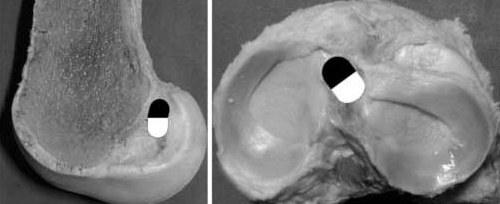

METHODS TO MEASURE PATELLA HEIGHT

Insall-Salvati 0.8-1.2 Blackbourne-Peel Ratio 0.5-1.0 Canton-Deschamps 0.6-1.3 Plateau-Patella angle 20-30 degrees is normal Blumensaats line should intersect inferior pole of patella at 30 degrees of flexion